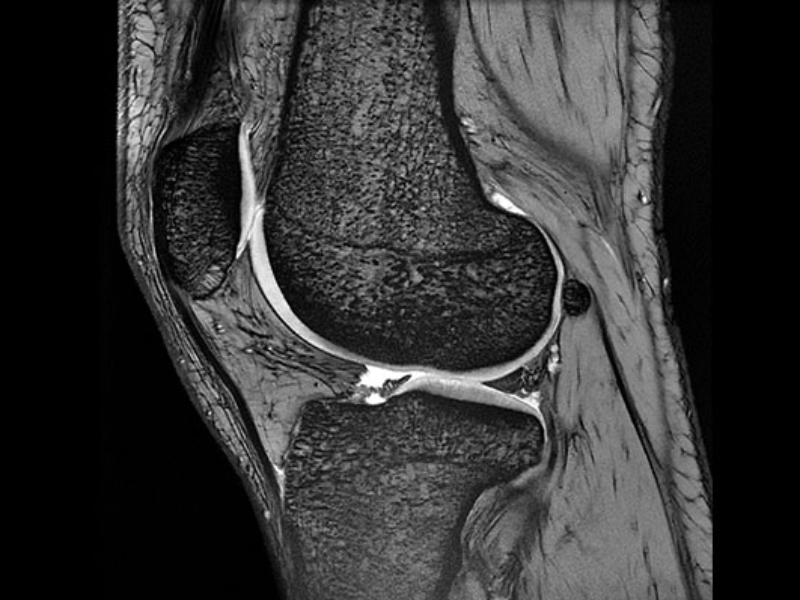

Sagittal 2D GRE of the knee